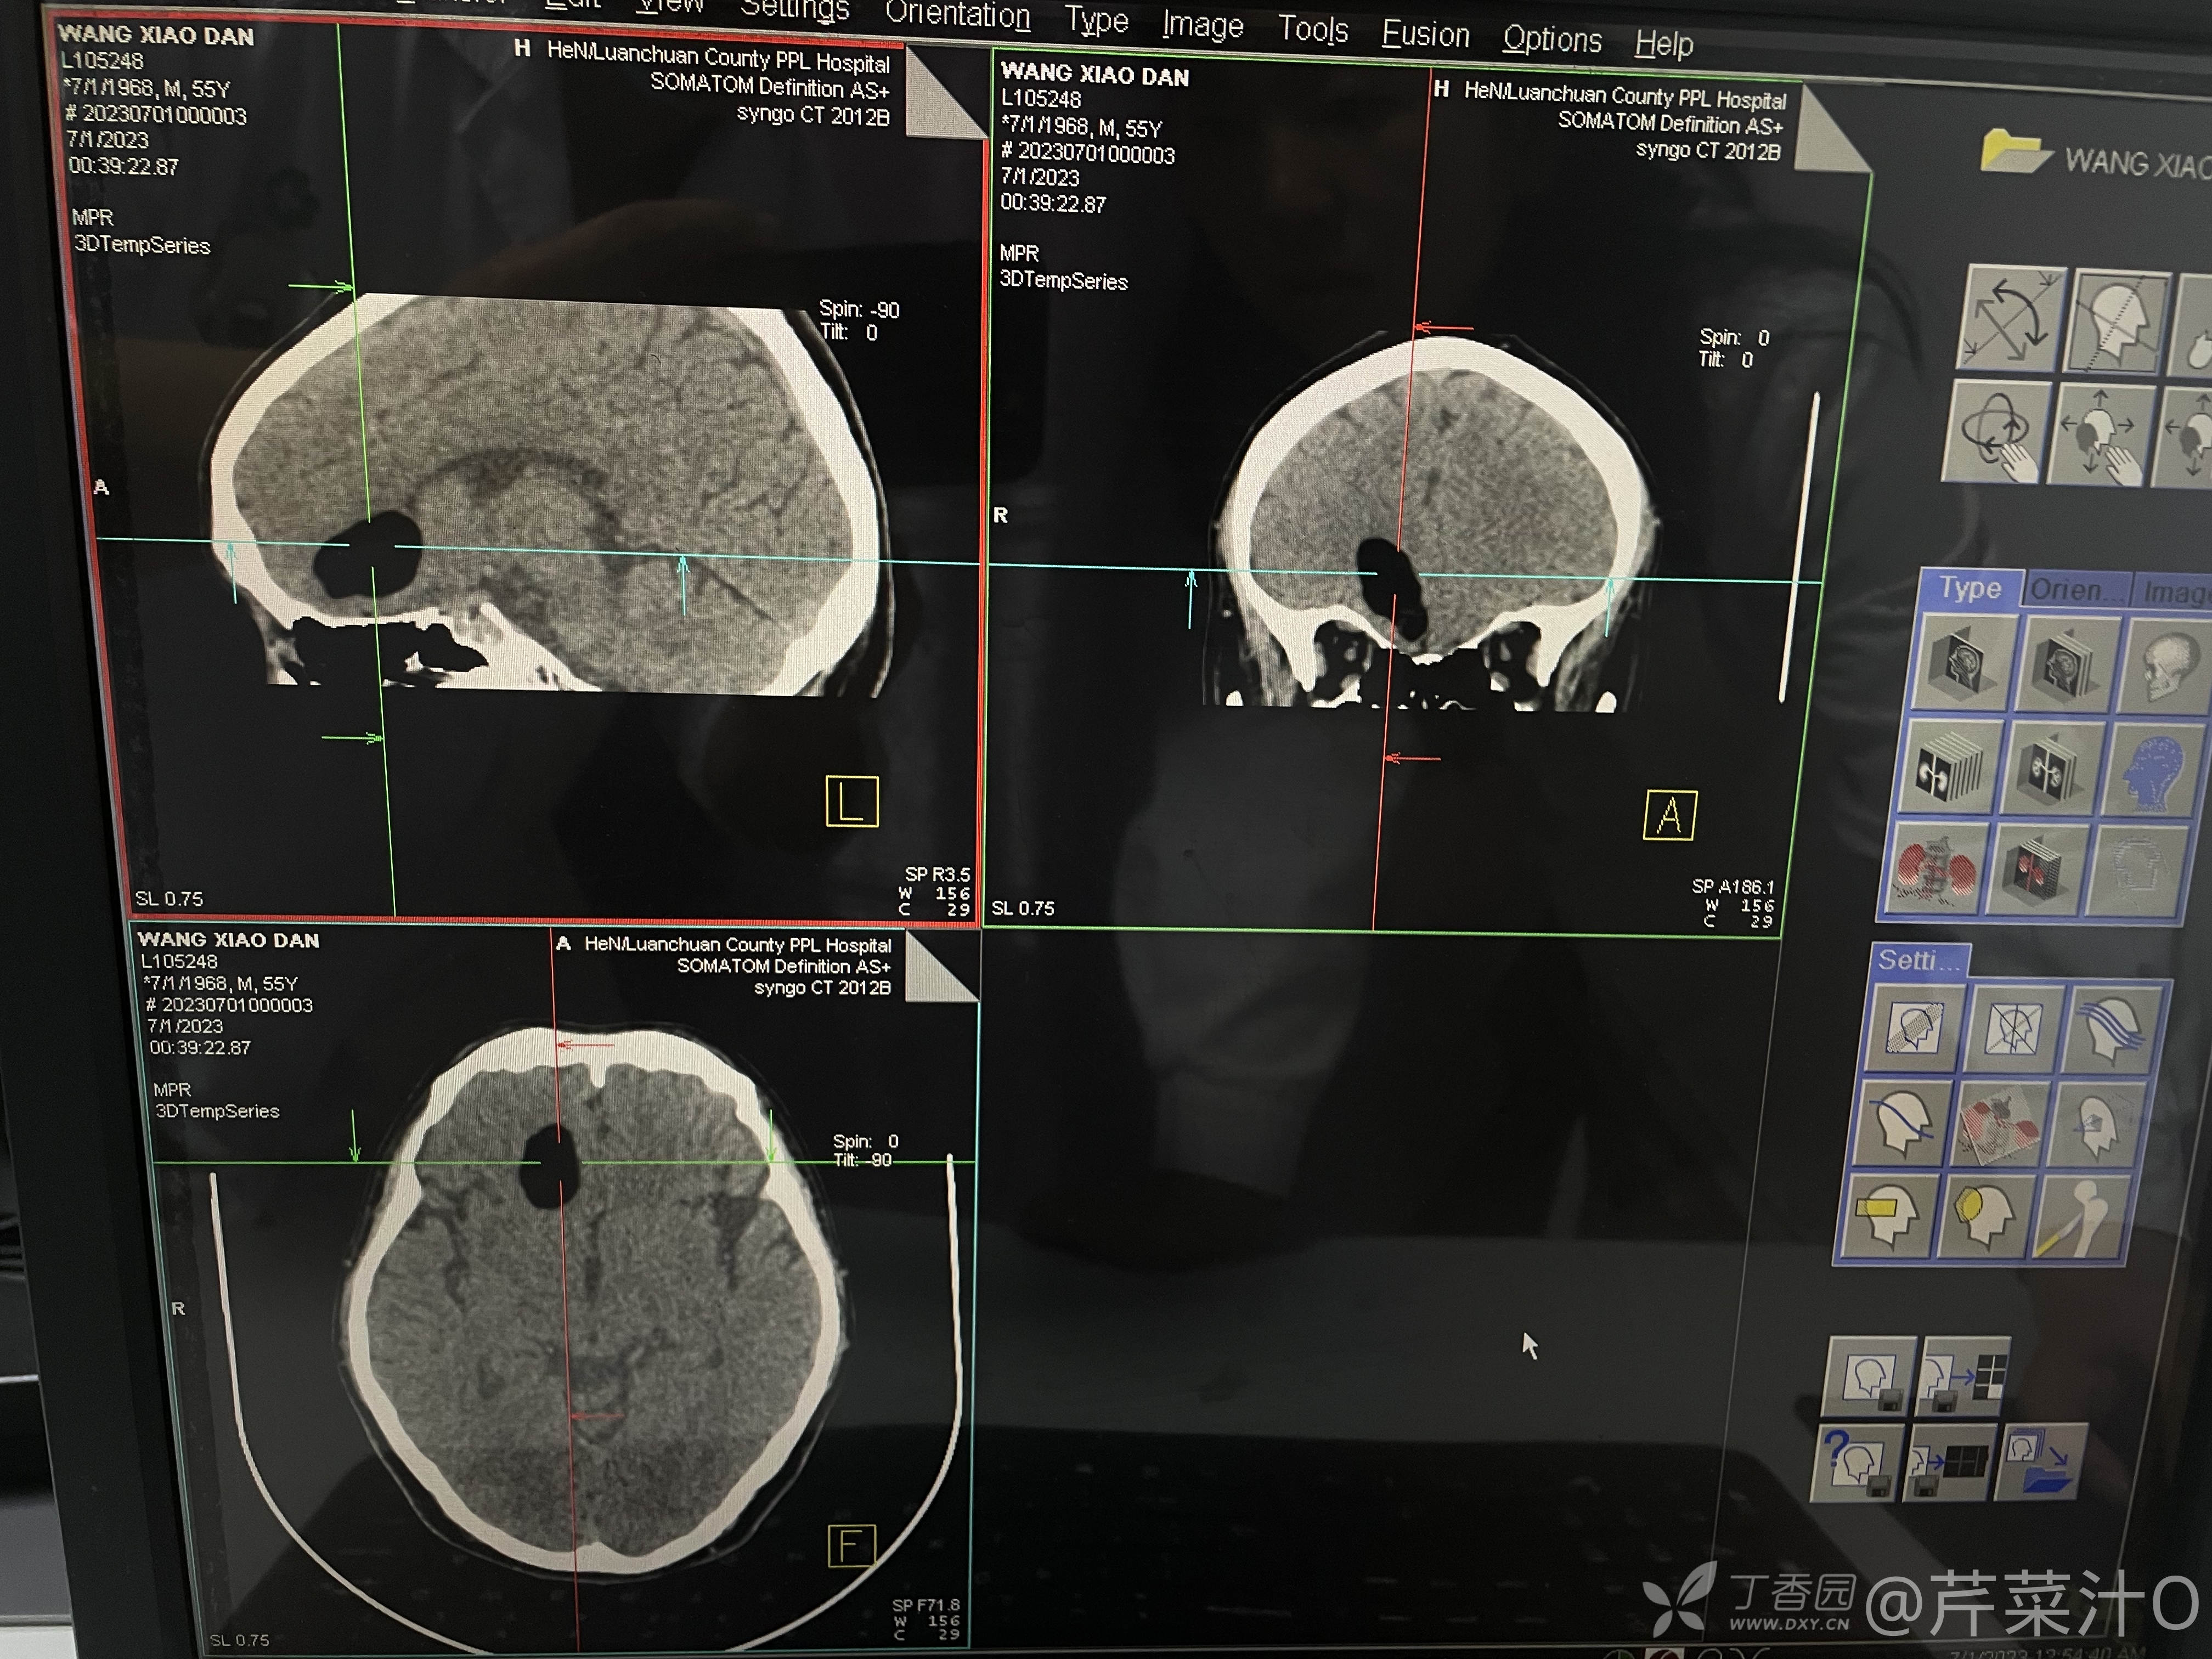

急诊暂完善血常规、电解质未见异常;头颅CT,MRI资料如下:

头颅CT提示局限性低信号